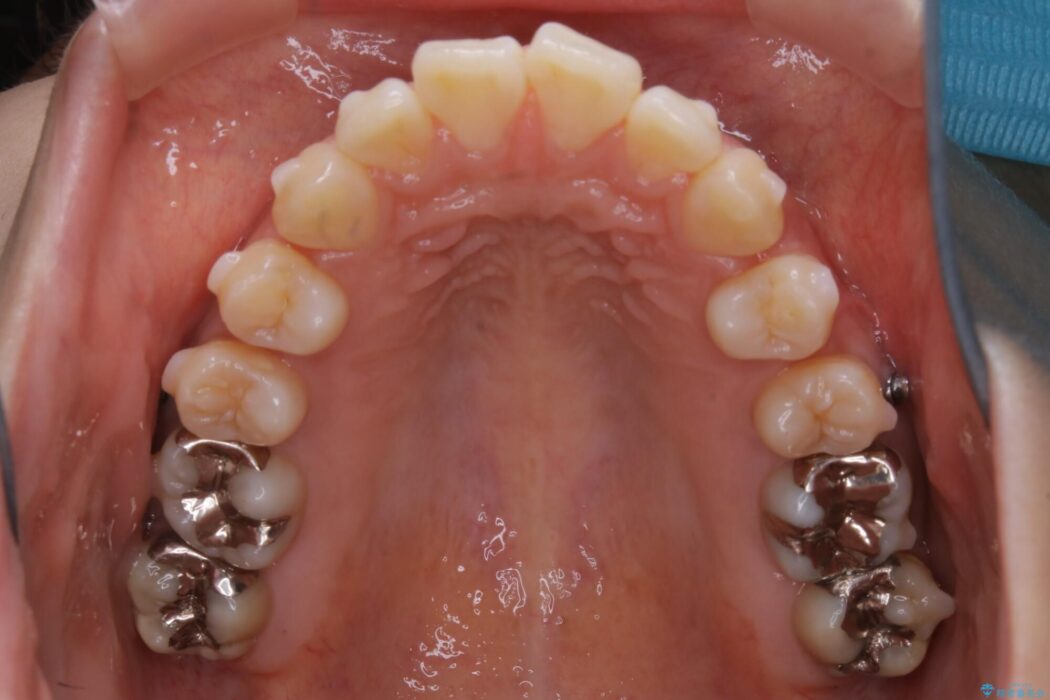

【20代女性】非抜歯でマウスピースの限界に挑戦する矯正治療

前歯を引っ込めるために非抜歯でのマウスピース矯正治療がしたいとの主訴で来院されました。

患者様からなおしたい内容をお聞きしたところ

・上下の歯のガタつき

・出っ歯感(口ゴボ)

・噛み合わせ

よって患者様ご希望の非抜歯かつマウスピースでの矯正を行うために、最大量の臼歯の遠心移動をして歯列全体を奥へ引っ込める計画をご提案しました。